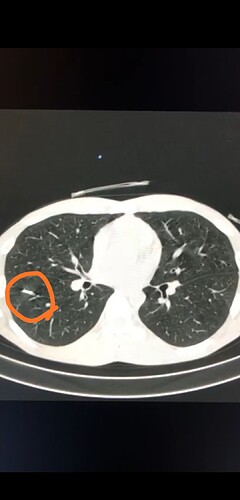

From the provided pictures, it was implanted into the right hand and ended up in the right lung lobe.

If it ātravelled along the venesā, as your doctors describe it, it would have had to go through the cephalic vein, into the axillary vein, through the branchiocephalic trunk into the superior vena cava, through the heart (right atrium and ventricle) and into the pulmonary artery, to get lodged in a lung capillary. Edit: incorrect assumption - please compare post #35

Edit: the thoracic MRI CT is pretty convincing, donāt get me wrong, itās just baffling

Thatās not it, you wanna look for the little foreign object on the left hand side that moves into view with some distorting rays from the CT scan or whatever.

@Pilgrimsmaster you are looking for this: